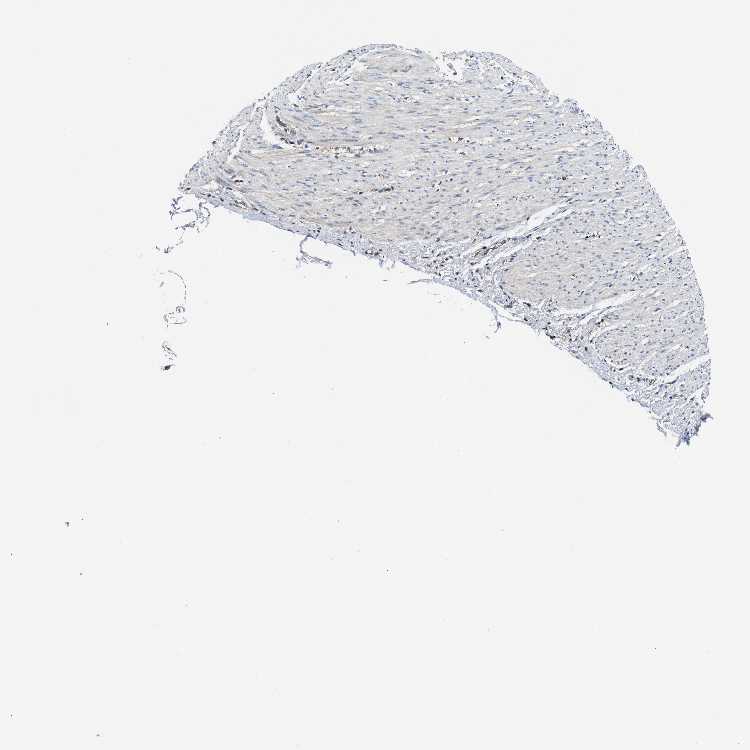

SOFT TISSUE 2 - Antibody stainingi

Antibody staining in the annotated cell types in the current human tissue is reported as not detected, low, medium, or high, based on conventional immunohistochemistry profiling in selected tissues. This score is based on the combination of the staining intensity and fraction of stained cells.

Each image is clickable and will lead to virtual microscopy that enables deeper exploration of all samples and also displays staining intensity scores, fraction scores and subcellular localization as well as patient and tissue information for each sample.

Antibody HPA020514

Fibroblasts High

Peripheral nerve Low